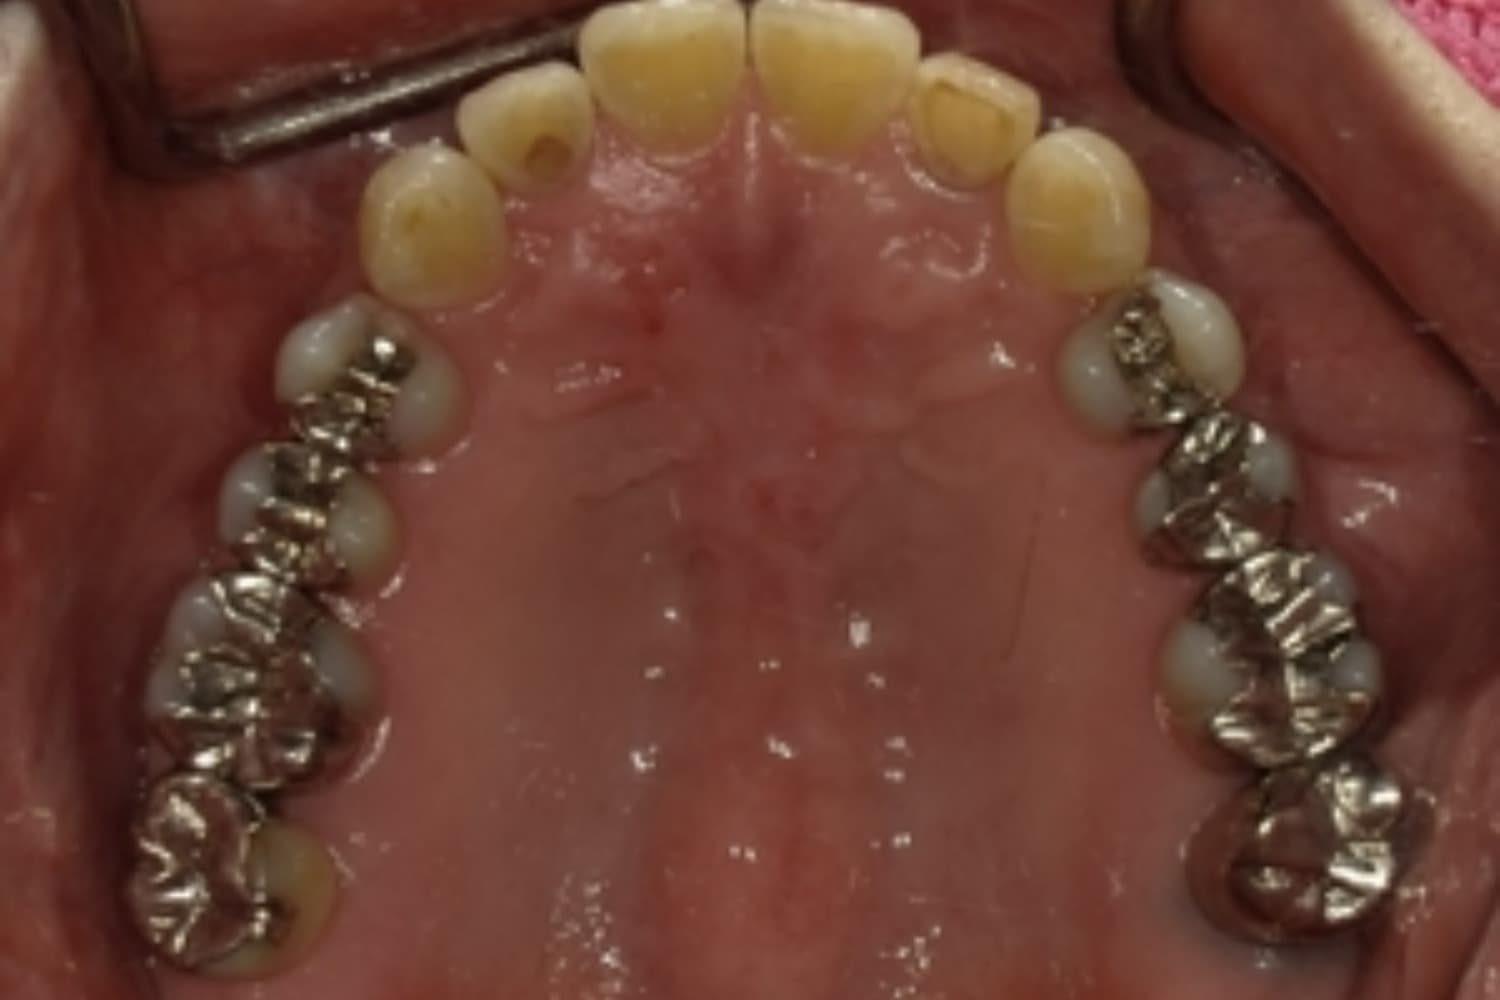

下顎大臼歯3本欠損症例

Before

After

左下第一大臼歯は保存が困難な状態であったため抜歯をおこないました。あわせて、ご来院時から欠損していた右下第一・第二大臼歯も含め、欠損部の補綴方法についてご説明し、インプラント治療を選択されました。

年齢

60歳

性別

男性

主訴

左下の第一大臼歯は別の医院で治療中でしたが、治療が思うように進まず、加えて他の箇所にも痛みが続いたことから、当院にご相談いただきました。

治療期間

10ヵ月

費用

140万円

副作用・リスク

インプラント治療は外科的な処置を伴い、多少の腫れや痛みが出ることがあります。 多くの場合は鎮痛薬で和らげることができます。